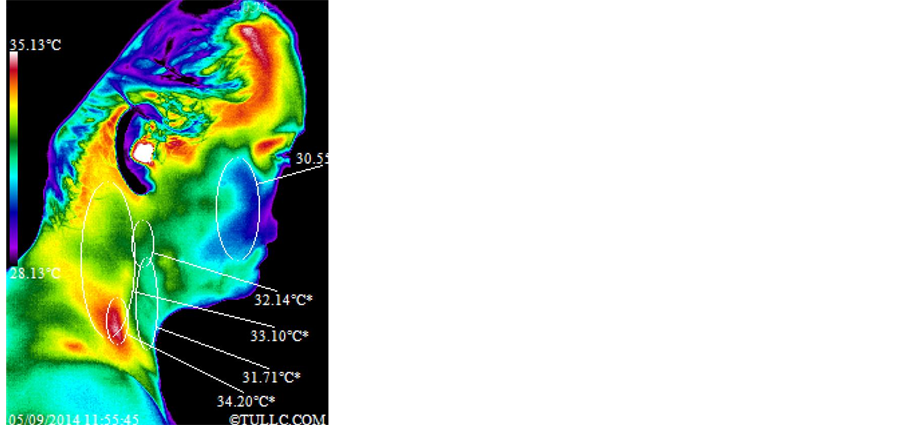

In Figure 4, Subject A’s facial thermal images were analyzed using a span of 7˚C and positioning between 28.13˚C and 35.13˚C. The color distribution, according to the modified Rainbow Chrome color palette, and the

7˚C span are displayed on the left side of each thermal image as explained previously (see Figure 1; this will be the case for all thermal images presented in this paper). After one hour of grounding, the temperature of the face increased significantly (31.67˚C - 31.05˚C = 0.62˚C). Statistical details of the image markers are presented in Table 1. Figure 5 top images show Subject A’s right lateral side and bottom images show Subject A’s left lateral side of the face before and after grounding. The temperature scale is the same as in Figure 4. Both lateral views reveal increased warmth throughout face and neck. Statistical details are presented in Table 2. Figure 6 shows full anterior views of Subject A’s torso before and after one hour of grounding. The span for these images is between 27.40˚C and 34.40˚C for the left image and 27.39˚C and 34.39˚C for the right image. This difference in span positioning of 0.01˚C (the sensitivity limit of the TI camera) between the before and after grounding images is small enough that it does not affect the comparison between the two images. For this subject, the entire anterior body clearly warmed up with the temperature of the region around the umbilicus showing a very significant increase (34.35˚C - 31.84˚C = 2.51˚C). Statistical details are presented in Table 4. For detail explanations of the significance of these temperature increases see the Discussion section.

Subject B’s facial thermal images were analyzed using a span of 7.01˚C and positioning between 28.22˚C and 35.23˚C. Figure 7 shows that the temperature of her face decreased significantly (32.54˚C - 31.95˚C = 0.59˚C). Statistical details of the image markers are presented in Table 1. Figure 8 top images show Subject B’s right

lateral views of the face and the images below those show left lateral views of the face before and after the grounding session. The span and positioning is the same as in Figure 7. Both sides of the face clearly cooled off. For example the marker of the right cheek decreased significantly (31.19 ˚C - 30.34˚C = 0.85˚C). Statistical details are presented in Table 2. Figure 9 shows full anterior views of the torso before and after the grounding session. This subject pointed a region of pain on the right side of the right breast near the arm pit, as shown by the circled letter “P” in the before picture of Figure 9. The span and positioning for these images is between 27.54˚C and 34.55˚C. The temperature of the abdomen increased but the temperature around the neck and shoulders decreased. Also the temperature of the right breast decreased while that of the left breast increased bringing them into an improved temperature symmetry. The temperature of the region around the umbilicus increased by exactly 0.5˚C (32.74˚C - 32.24˚C = 0.5˚C). Statistical details are presented in Table 4 and interpretation of patterns in the Discussion section.

All markers of Figure 4 increased in temperature after the grounding session. This is due to the entire torso surge of lymphatic/venous flow routing lymphatic fluids via the inferior vena cava/right subclavian vein/thoracic duct into the left subclavian vein. The upper torso fluids are also routed to the heart via the superior vena cava. This happened while grounded in order to produce a physiological homeostasis/stabilization of core temperature. This subject had what appears to be a purging of lymphatic/venous congestion that not all subjects experienced. As in Figure 4, all markers of Figure 5 increased in temperature. Significant overall head/neck increased temperatures appear to be related to cranial fluids competing with torso fluids that are being overly dumped into the same veins [14] - [17] .